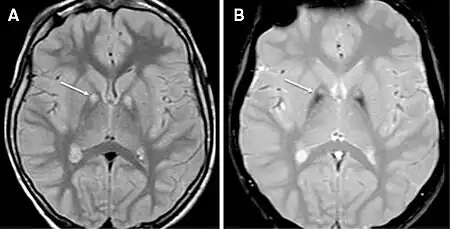

| MRI of a individual with pantothenase kinase-associated neurodegeneration | |

DaT scans, transcranial Doppler sonography (TCD), PET scans, and, in some cases, magnetic resonance imaging (MRI) (type of scans depending on the symptoms)[16] are used to distinguish between the different forms of NBIA due to the accumulation of iron in different areas of the brain.[17] Patients typically fall into two different categories: (1) early onset, rapid progression or (2) late onset, slow progression.[17] The first type is considered to be the classic presentation, while the second type is thought to be a more atypical presentation. Phenotypes of the different disorders appear to be dependent on age, i.e. amount of iron accumulation and cognitive abilities.[18]